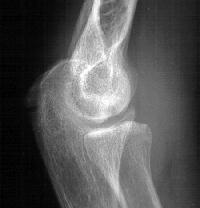

Initial injury: supracondylar fracture in a 9 year old:

Plain films show humeral osteophytes and posttraumatic changes of the capitellum and radial head.